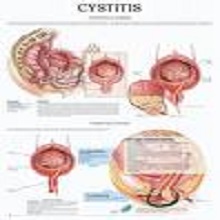

Уринарну инфекцију пре свега потврђују њени симптоми који су веома непријатни. Јављање тегоба уколко не пролази захтева посету лекару. Уринарне инфекције су чешће лети и код жена, за то је често може бити одговоран мокар купаћи или клима уређаји |

| Инфекције мокраћних путева (ИМП) су један од водећих разлога за прописивање антибиотика у свету. Најчешће су у доби од 18 до 39 година, када је сексуална активност највећа. Посебно су честе код младих жена и чак 27% њих 6 месеци након прве епизоде ИМП има потврђен први, а 2,7% потврђен и други рецидив. |

Инфекције уринарног тракта су честе у детињству. Могу се јавити код свих узраста деце и захватити различите делове уринарног система. Чешће су код девојчица него код дечака, а према узрасној групи су најчешће код деце до 5 година живота. |